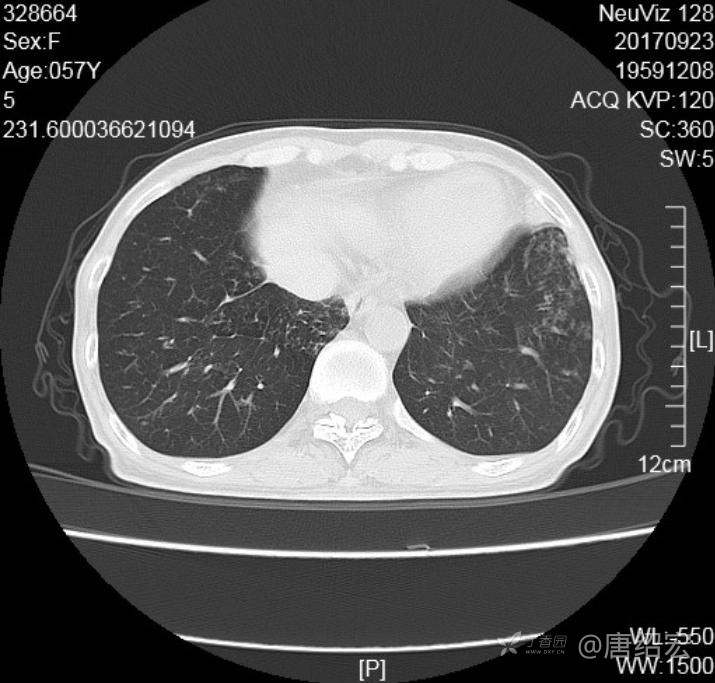

中年女性满肺树芽征还有支气管扩张,考虑什么疾病?

女,57岁,

主诉:发热、咳嗽、咯黄痰,胸闷3天入院。